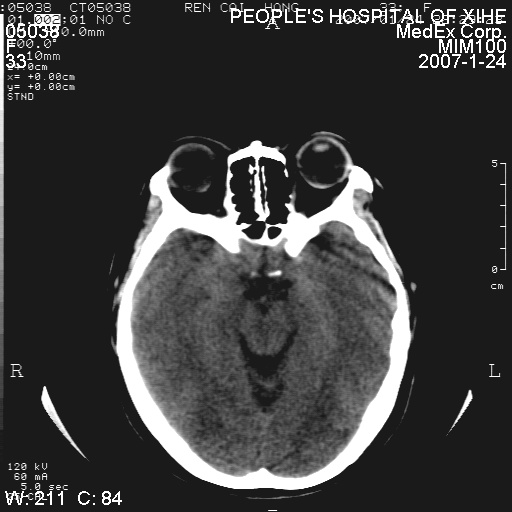

以下是引用xclzq_910在2007-1-25 12:41:00的发言:[br]左额叶条片状低密度灶,考虑占位,建议增强